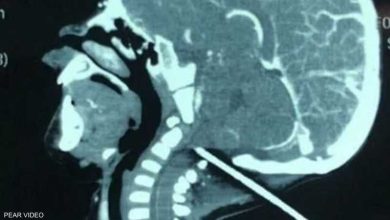

قضيب حديدي يخترق جمجمة رضيع.. و”معجزة” تنقذه

النقابي الجنوبي/متابعة خاصة اخترق القصيب الحديدي جمجمة الرضيع كان رضيع يبلع من العمر عاما واحدا يلهو في في ساحة منزله عندما انزلق فجأة، ولسوء حظه وقع على قضيب حديدي بارز انغرز في جمجمته. وفي التفاصيل التي أوردتها، صحيفة “ديلي…